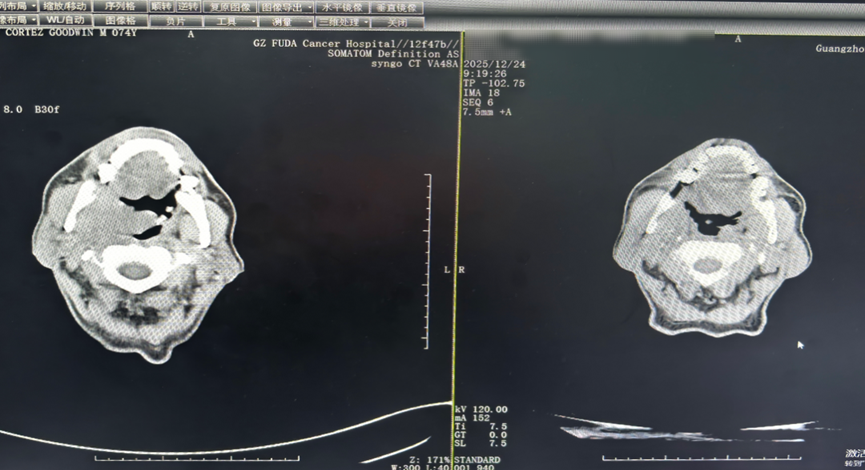

△ ภาพเปรียบเทียบ CT หลังการรักษา 2 คอร์ส พบว่าก้อนมะเร็งบริเวณคอหอยและก้อนที่ลำคอลดขนาดลงอย่างชัดเจน